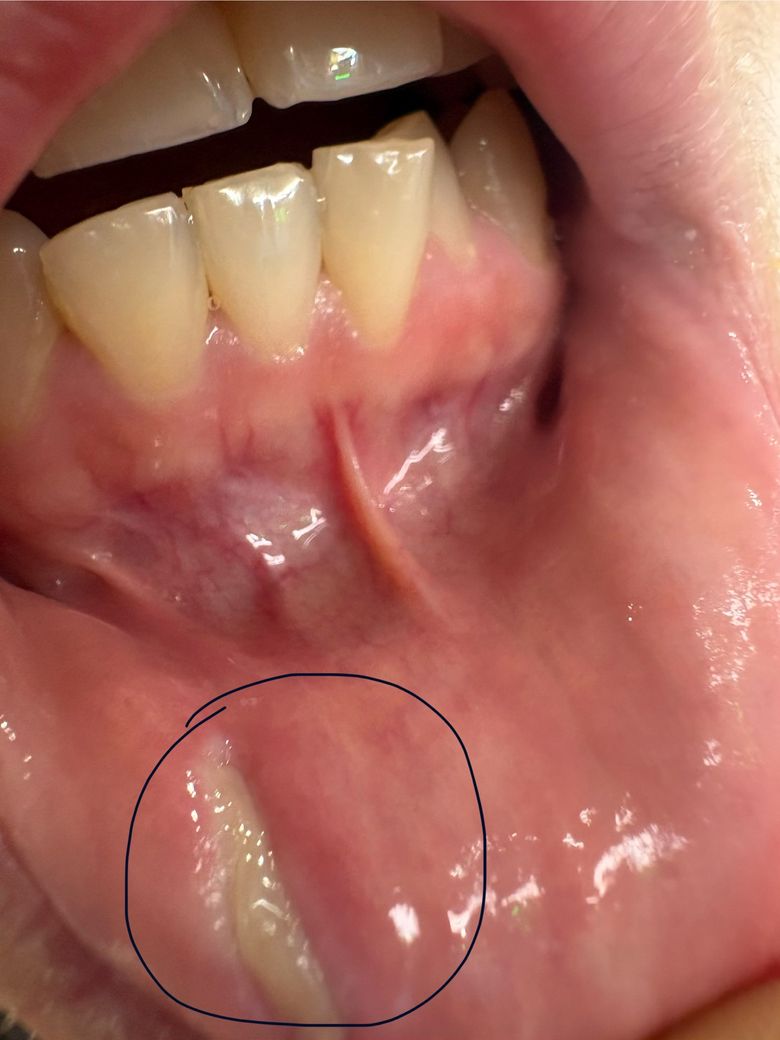

상처에 새살이 올라고 있습니다 완벽히 회복되는 시간이 궁금합니다

어제 부터 새살이 조금씩 올라오고 있습니다

혹시 몇일이 더 있어야 완벽히 상처가 회복이 될까요?

보통 새살이 완벽히 덮는데 까지 시간 얼마나 걸리나요?

상처가 꽤 깊었나 봅니다. 그냥 놔두셨던 것 같구요. 새살은 차 올라온 상태라고 보여지고 원래의 점막 처럼 보이려면 1주일 정도는 더 필요할 것 같아요. 상처가 좀 깊었어서 점막임에도 좀 시간은 걸리지 않을까 싶어요.